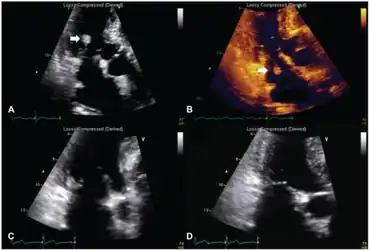

a,b) Transthoracic echocardiography - NBTE arrow c.d) after anticoagulation therapy lesion practically disappeared

Diagnosis may be made by echocardiography; however not all emboli are obvious.[1] There is no effective treatment, but anticoagulation is often used.[1]